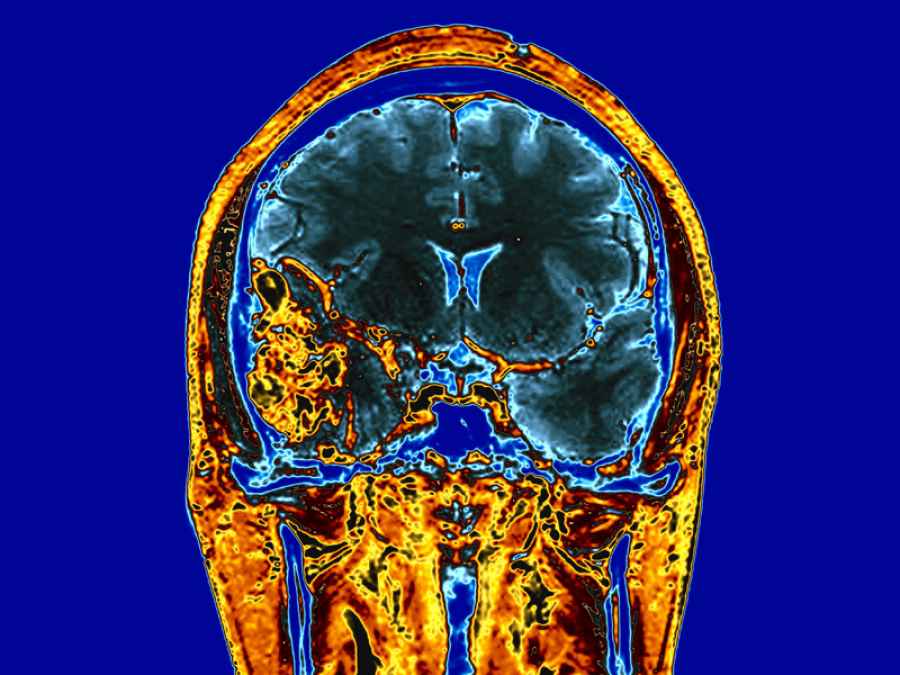

El gadolinio, que se usa como medio de contraste en las resonancias magnéticas, si se reparte dentro de las células cancerígenas podría acabar con ellas mediante la liberación de electrones tras ser golpeadas por rayos X, según una investigación publicada en la revista ‘Scientific Reports’ y cuyo objetivo es buscar la manera en que la radioterapia solo actúe sobre las células cancerosas.